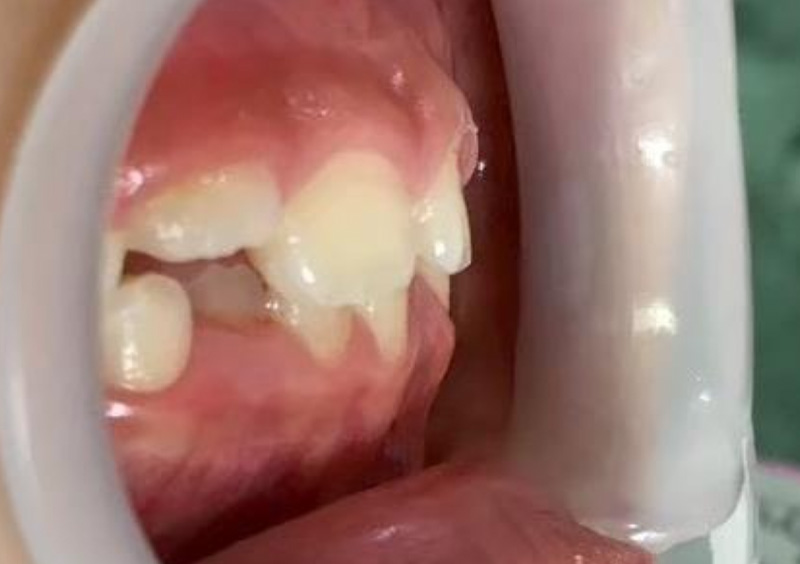

子供の矯正治療 大人の歯が生えてくるスペースがない 2026.03.19 【プレオルソ】大人の歯が生えてくるスペースがない 治療前 治療後 担当医 一瀬 悠依華 先生 主訴 大人の歯が生えてくるスペースがない 期間 4年 費用 35万円(小児矯正) 治療内容 プレオルソ 治療に伴うリスク 歯根吸収、歯肉退縮 関連症例